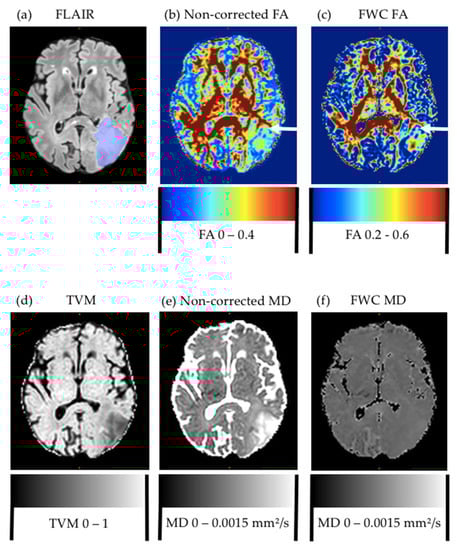

Visual comparison of standard and free-water-corrected FA maps revealed a relevant recovery of FA information, especially in areas with large partial volume contamination, such as peritumoral edema and the borders of the ventricles, leading to a visual improvement of FA maps (Figure 1). This recovered new information about tissue-microstructure integrity, previously hidden by the edema, which motivated us to further evaluate the utility of this information for predicting tumor recurrence.

Figure 1. Comparison of metrics for glioblastoma patient. Preoperative FLAIR (a) with edema segmentation (overlaid in blue), and (b) noncorrected and (c) free-water-corrected fractional-anisotropy (FA) maps. Arrow in both FA maps points to area of later tumor recurrence. For improved visualization, display windows were adapted. (d) Tissue-volume map with generally lower values in peritumoral edema, but no significant differences between pure edema and edema with later recurrence. Mean-diffusivity map (e) before and (f) after free-water correction, which noticeably decreased contrast.

In contrast to FA values, MD values did not reveal additional information about the peritumoral edema and later recurrence after performing free-water correction. In general, MD values can perfectly describe isotropic diffusion but not the whole properties of anisotropic diffusion [22]. In most brain tumors, when compared to normal brain tissue, the diffusion coefficient is elevated [7]. Concerning the recurrence prediction and classification of primary brain tumors, prior studies found that there is a decrease in MD or apparent diffusion coefficient (ADC) in areas of peritumoral edema that showed later recurrence [23], as well as decreasing ADC values with an increasing World Health Organization (WHO) grade [24]. This made us investigate potential changes in MD values after free-water elimination. However, we only observed a small difference in the 90th percentile. As expected, MD values were lower in areas of later recurrence. Given that free water is basically the source of contrast in MD, we expected to lose signal through free-water correction. Given this decreased contrast in MD images (see Figure 1), different methods of DTI processing might be more suitable for MD data analysis. More research should be undertaken to detect possible further potential of MD in evaluating tumor infiltration.